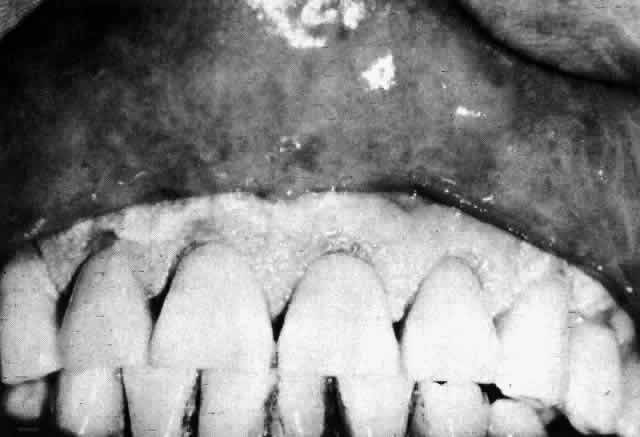

The eye may be affected in toxic epidermal necrolysis (Figs. 8 and 9). A mucopurulent conjunctivitis is the most common lesion, but symblepharon, eyelid changes, and corneal complications may develop in severe cases. Other causes include viruses, malignancies, graft-versus-host disease, and vaccines.32

Fig. 8. Extensive “burnlike” skin lesions in toxic epidermal necrolysis. (Courtesy of Dr. HB Ostler)

Fig. 9. Eyelid involvement in toxic epidermal necrolysis. (Courtesy of Dr. HB Ostler)